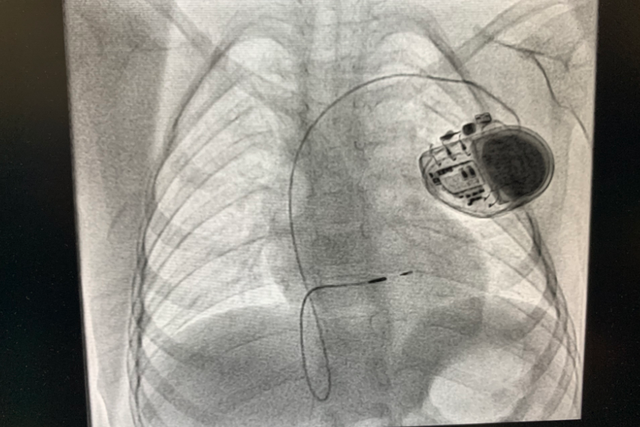

5月6日,广东药科大学附属英德医院(广东省英德市人民医院)成功完成英德地区首例无导线起搏器Craic AV植入。该无导线起搏器植入的落地,标志着心内科在心律失常诊治方面取得新突破。

在心内科骆嵩山主任的组织下,专家团队们经过术前综合分析,考虑到患者为老年女性,二度房室传导阻滞、高度房室传导阻滞、三度房室传导阻滞交替出现,排除了冠心病、高钾、食物药物导致等诱发因素,起搏器植入治疗指征明确。但患者双上肢严重畸形及双侧锁骨下静脉入路异常,曾经尝试行传统起搏器植入手术失败。目前情况下,只有最新的起搏技术---无导线起搏器植入术才可能成功为患者进行起搏治疗。经与患者和家属进行了充分的沟通后,最终选定治疗方案,手术植入Micra无导线起搏器。

Micra无导线起搏器的手术在局部麻醉下进行,手术时间仅用时30分钟左右,患者术后反应良好,术后2~3天后即可恢复正常的状态出院。

和传统起搏器不同,无导线起搏疗法Micra,创新的无导线,无囊袋设计,可以大大减少并发症发生的风险。无导线 “起搏胶囊”Micra体积更小,仅如维生素胶囊一般大,重量仅约2g。同时拥有超强的电池续航能力---寿命预计超过12年,同时兼容3.0T核磁共振扫描的创新功能,植入后MRI扫描也没有限制。